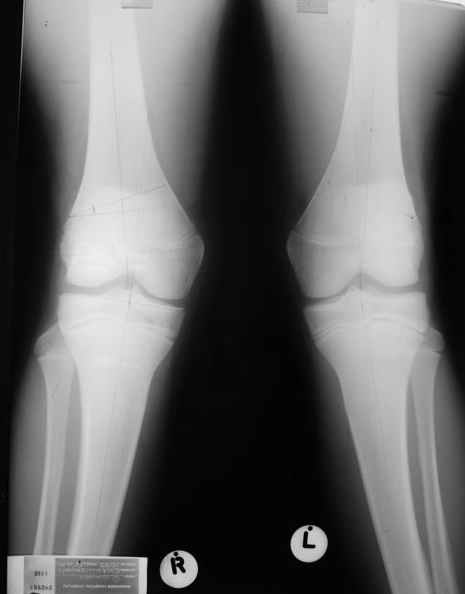

Уважаемый Евгений ! Спасибо за ответ, но мне представляется, что в нашем случае основной проблемой является не столько прогрессирующий вальгус конечности, сколько несросшийся перелом мыщелка бедра и дефект мыщелка большеберцой кости - вероятно первичная репозиция выполнялась без пластики.

Мне представляется, что прогрессирующий вальгус и обусловлен несросшимся переломом мыщелка бедра (томограммы -зона межфрагментарного склерозирования), а циклические нагрузки на сустав во время ходьбы усугубляют ситуацию. Как вы думаете, в этой ситуации насколько вероятен риск развития аваскулярного некроза мыщелка бедра?

Относительно "рубцовой подушки" я имел в виду остатки мениска ( частично вколоченного в дефект мыщелка и фрагменты хряща), все таки на рентгенограммах суставная щель в этом отделе чем то заполнена. Что касается некроза мыщелка бедра, то мне кажется он уже наступил - томограмма ноябрь5.

С учетом всего сказанного - наличия прогессирующего вальгуса конечности, довольно приличного объема движений, имеющегося, вероятно, некроза мыщелка бедра, наиболее рациональным представляется удалить пластину с б\б кости, произвести остеотомию б\б кости с коррекцией вальгуса, разгрузив тем самым наружный отдел сустава, и синтезировать фрагменты голени накостным фиксатором. Максимально тано начать восстановление движений в суставе. Скорее всего рано или поздно речь о протезировании всеже возникнет, но мы хотя бы будем иметь приличную ось конечности.

Тут ситуация совсем другая. Деформация не около-, а самая что ни на есть внутрисуставная. Покорректировать внешний вид конечности путем остеотомии дистального отдела бедра и high tibia (плюс или минус клин, одномоментно-постепенно, аппарат-пластина-стержень - дело третье) не сильно сложно, но это не решение проблемы. У больной, по

сути отсуствует латеральный отдел коленного сустава, что требует костно-пластических вмешательств непосредственно на артикулирующих

поверхностях.

Может быть, целесообразней сразу протез, чем тот же протез, но после сложных, но сомнительно результативных операций типа замещения алломыщелком, моделирующих резекций и т.п.? Ну и в любом случае движения лучше бы разработать получше до любой операции.

Сравни состояние артикулирующих поверхностей в представленном тобой примере и обсуждаемом случае.